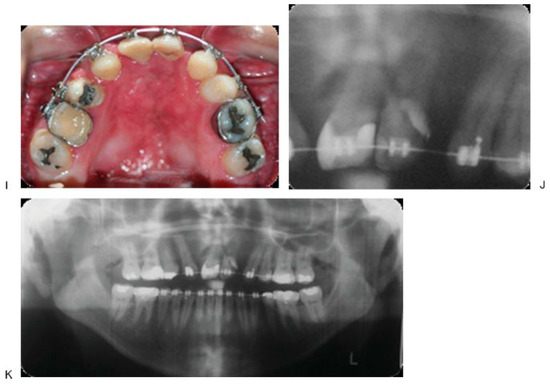

Figure 3. Initial aspect (A–E). Design of the device (F). End bifocal alveolar bone transportation technique (G). Closing of alveolar fistula at 57 weeks of follow-up (H–J). Regenerated new bone behind of the used transport disk (K). - Case 2 was a 16-year-old female patient with sequel of cleft lip and palate and active oronasal fistula, treated with bifocal ABT (Figure 4).

Figure 4. Initial aspect (A–D). There is no anchoring of dental bands, but orthodontic tubes (E). End trifocal alveolar bone transportation technique (F). Aspect at 90 weeks of follow-up (G,H), and radiographics with evidence of closure fissure and osseointegrated implant in the regenerated new bone (I–K). - Case 3 was a 19-year-old male patient with sequel of cleft lip and palate and active oronasal fistula, treated with bifocal ABT (Figure 5).